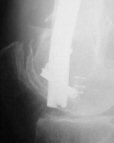

Attached are few examples from our Hospital:

B. Fixation loosening: distal cutting of the nail, non-unions do happen (cases attached).

Locking Plating has more distal screws than any nail, fixed angles and provides much better fixation, especially in osteoporotic bone.